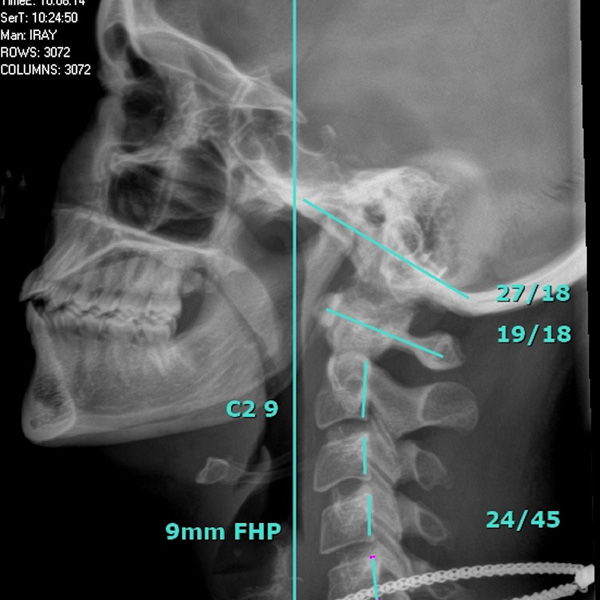

Advanced X-Ray Analysis involves a detailed examination of digital x-rays to identify misalignments, abnormalities, and structural imbalances in the spine. This comprehensive assessment goes beyond surface-level symptoms, enabling us to pinpoint the root causes of pain, disease, and dysfunction. By analyzing each patient’s x-rays, we gain critical insights into their spinal structure, which helps us develop a treatment plan tailored to correct the problem from its root.

X-Rays are a powerful diagnostic tool that provides a clear picture of the spine’s condition. They allow us to see beyond what’s visible during a physical examination, uncovering issues such as vertebral subluxations, disc degeneration, or abnormal curvatures. This information is crucial for creating a personalized care plan that addresses each patient’s unique challenges.

X-rays are a powerful diagnostic tool that provide a clear picture of the spine’s condition. They allow us to see beyond what’s visible during a physical examination, uncovering issues such as vertebral subluxations, disc degeneration, or abnormal curvatures. This is crucial for creating a personalized care plan that addresses each patient’s unique challenges.